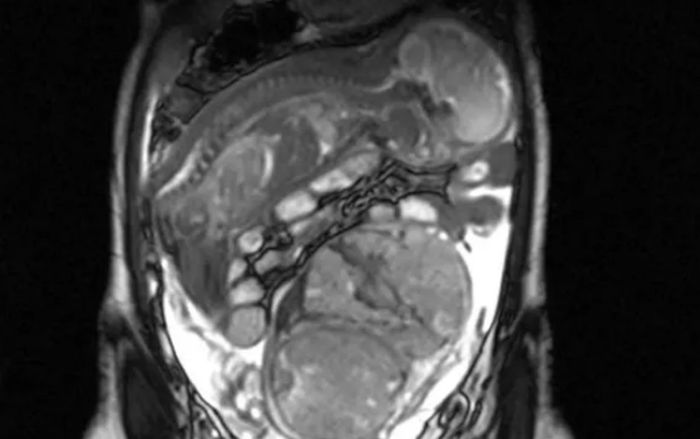

Đi khám thai, người phụ nữ 30 tuổi sốc khi số lượng em bé trong bụng thay đổi mỗi lần siêu âm